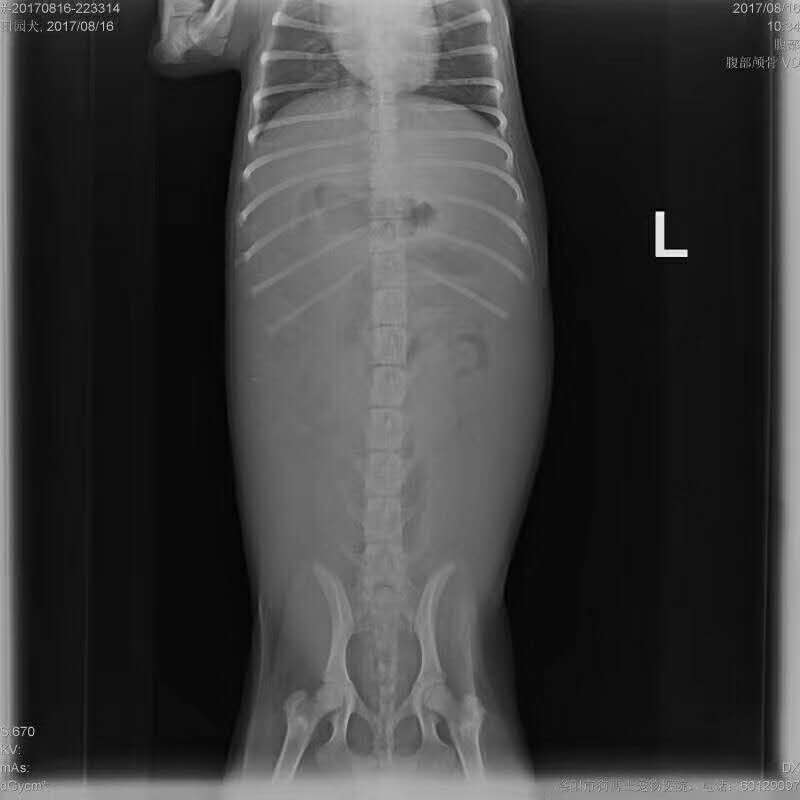

車禍導(dǎo)致膀胱破裂實(shí)施手術(shù):      小花,田園犬,母,前天被電動(dòng)車撞傷,腹腔積液/脹大,牙齦顏色粉紅   無食欲,喝水,主人不確定有沒有見尿,經(jīng)DR,B超等化驗(yàn)發(fā)現(xiàn)膀胱較小,膀胱完整性缺失,初步診斷膀胱破裂,實(shí)施手術(shù)修復(fù)   已蘇醒,狀態(tài)穩(wěn)定